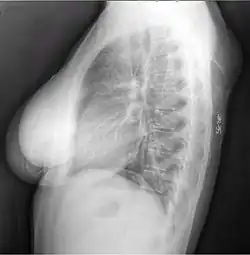

-

X-ray of a lipoma -

X-ray showing lipoma -